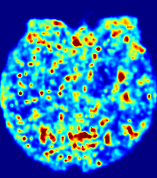

Figure 12: PIANO effectiveness and robustness testing: advection imaging via advection. Top row shows the ground truth 𝐕gt2subscriptnormsuperscript𝐕gt2\|{\bf{V}}^{\text{gt}}\|_{2} used for simulating pure advection. (a)-(f) refer to the results for 𝐕2subscriptnorm𝐕2\|{\bf{V}}\|_{2} estimated by PIANO, with simulated advection imaging series where Rician noise at levels 0%, 2%, 4%, 6%, 8%, 10% was added respectively.

We further simulate noisy concentrations by adding Rician noise [24] with variances equalling 2%, 4%, 6%, 8%, 10% of the originally simulated concentrations {Cti}superscript𝐶subscript𝑡𝑖\{C^{t_{i}}\}. We then test how well PIANO can estimate the underlying velocity field via Eq. 15 with the same model settings (except without estimating the diffusion) as in Sec. 3 given the original and the noisy concentration time-series. Fig. 12 shows the estimated 𝐕est2subscriptnormsuperscript𝐕est2\|{\bf{V}}^{\text{est}}\|_{2} for one patient. Fig. 11 (a) shows the summarized estimation results for all 43 patients. PIANO almost perfectly captures the underlying velocity field, and maintains excellent performance even when estimating from concentrations with varying noise levels.